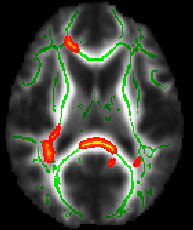

You will probably next want to load the mean_FA_skeleton image on top of your background image, to show where the skeleton was estimated, and which standard-space voxels were tested in the multi-subjects statistics. Load mean_FA_skeleton into FSLeyes and set its display range correctly. The lower threshold must be set to the threshold that you used in the TBSS analysis, for example 0.2. The upper level should probably be set to something like 0.7, so that you can see variation in mean FA values within the skeleton. You probably want to change the colourmap, for example to Green, and increase the transparency (with the transparency slider) so that when you load the stats image in, it is easier to see.

Finally, load the stats image in. If you have used TFCE-based testing in randomise, the raw t-statistic image will be named something like tbss_tstat1 (which you could view to see raw tstats before significance testing), but the image you probably want is tbss_tfce_corrp_tstat1, which is the corrected p-value image (actually the values in this image are 1-p for ease of display, so that bigger is "better"). Load this into FSLeyes, set a colourmap such as Red-Yellow, and set the display range to something like 0.95 to 1, which corresponds to thresholding the results at p<0.05.

All of the above (apart from setting the skeleton transparency, which has to be done by hand in the GUI) can be carried out with a single command (see first example image):

fsleyes $FSLDIR/data/standard/MNI152_T1_1mm mean_FA_skeleton -cm green -dr 0.2 0.7 tbss_tfce_corrp_tstat1 -cm red-yellow -dr 0.95 1